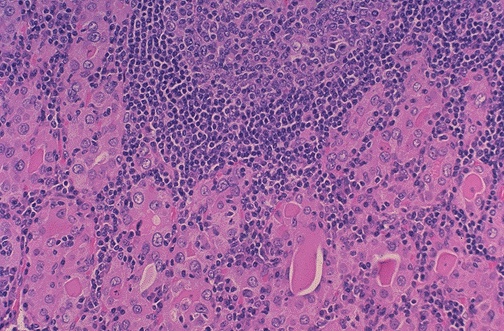

Image 5.4

What changes are present at higher power?